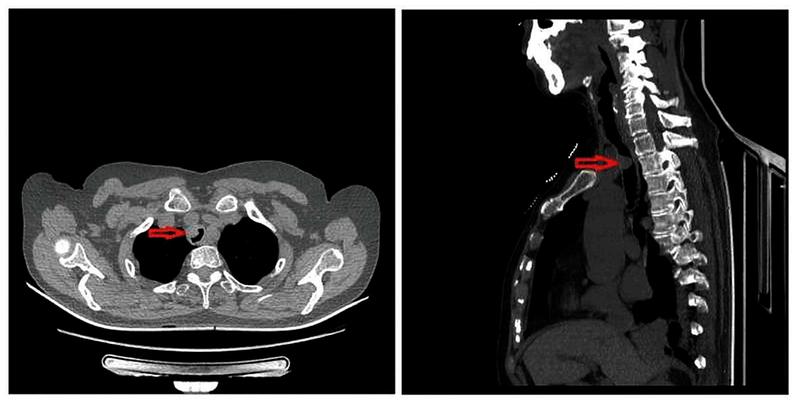

图1胸部CT及支气管三维重建提示主气道肿物

71岁的女性患者王某,因“胸闷气短1月余”于2020年08月31日入住我院胸外科。胸部CT及支气管三维重建提示主气道肿物(图1),气管镜检查提示距声门6cm、隆突上5cm处隆起性病变,位于胸锁关节后方,占据管腔60%,取病理活检提示“粘膜腺样囊性癌”(图2)。经过术前检查排除手术禁忌后李少民主任邀请急诊科、麻醉科等相关科室进行多学科会诊,遂决定行在ECMO配合喉罩通气下行气管肿瘤切除、气管吻合术。9月9日上午,患者进行全身麻醉后,急诊科团队立即进行VV-ECMO连接,确保患者术中血氧的维持,随后胸外科李少民主任、马跃峰副主任医师团队进行手术操作,术中见肿瘤位于右头臂干及左颈总动脉后方,牵开双侧动脉充分游离并显露气管肿瘤位置,完整切除了肿瘤位置的气管,共切除4个气管环,长度约3cm(图3),并成功完成主气管上下残端吻合(见图4),手术过程顺利,术后患者生命体征平稳,顺利脱离ECMO、去除喉罩后安全返回胸外科监护室,目前患者病情稳定。